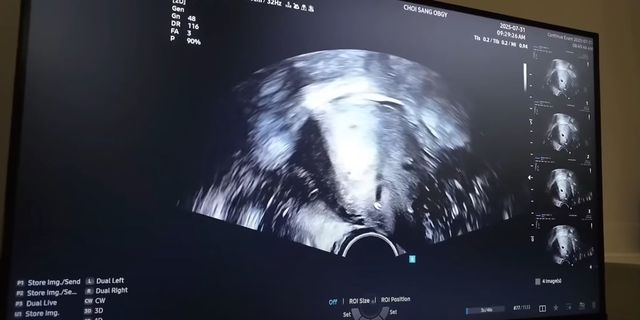

그는 “오늘로 임신 10주 2일 차, 소중한 두 아이를 소개한다”며 “조산 위험이 있어 배아를 1개만 이식했는데 자연 분열로 일란성 쌍둥이가 됐다. 확률이 1%에 불과하다고 한다”고 설명했다. 이어 “처음엔 두려움이 앞섰지만 지금은 건강하게 출산하겠다는 마음뿐”이라며 “저와 비슷한 상황에 있는 분들께 작은 희망이 되고 싶다”고 덧붙였다.

오늘로 10주 2일차,

소중한 두 아이 하트와 큐트 일란성 쌍둥이를 소개합니다!!

저는 경부가 없어 조산위험이 있어

일부러 배아를 1개만 이식을 했는데도

스스로 자연 분열해 일란성 쌍둥이가 되었어요

1%확률이라고 합니다..ㅎㅎ